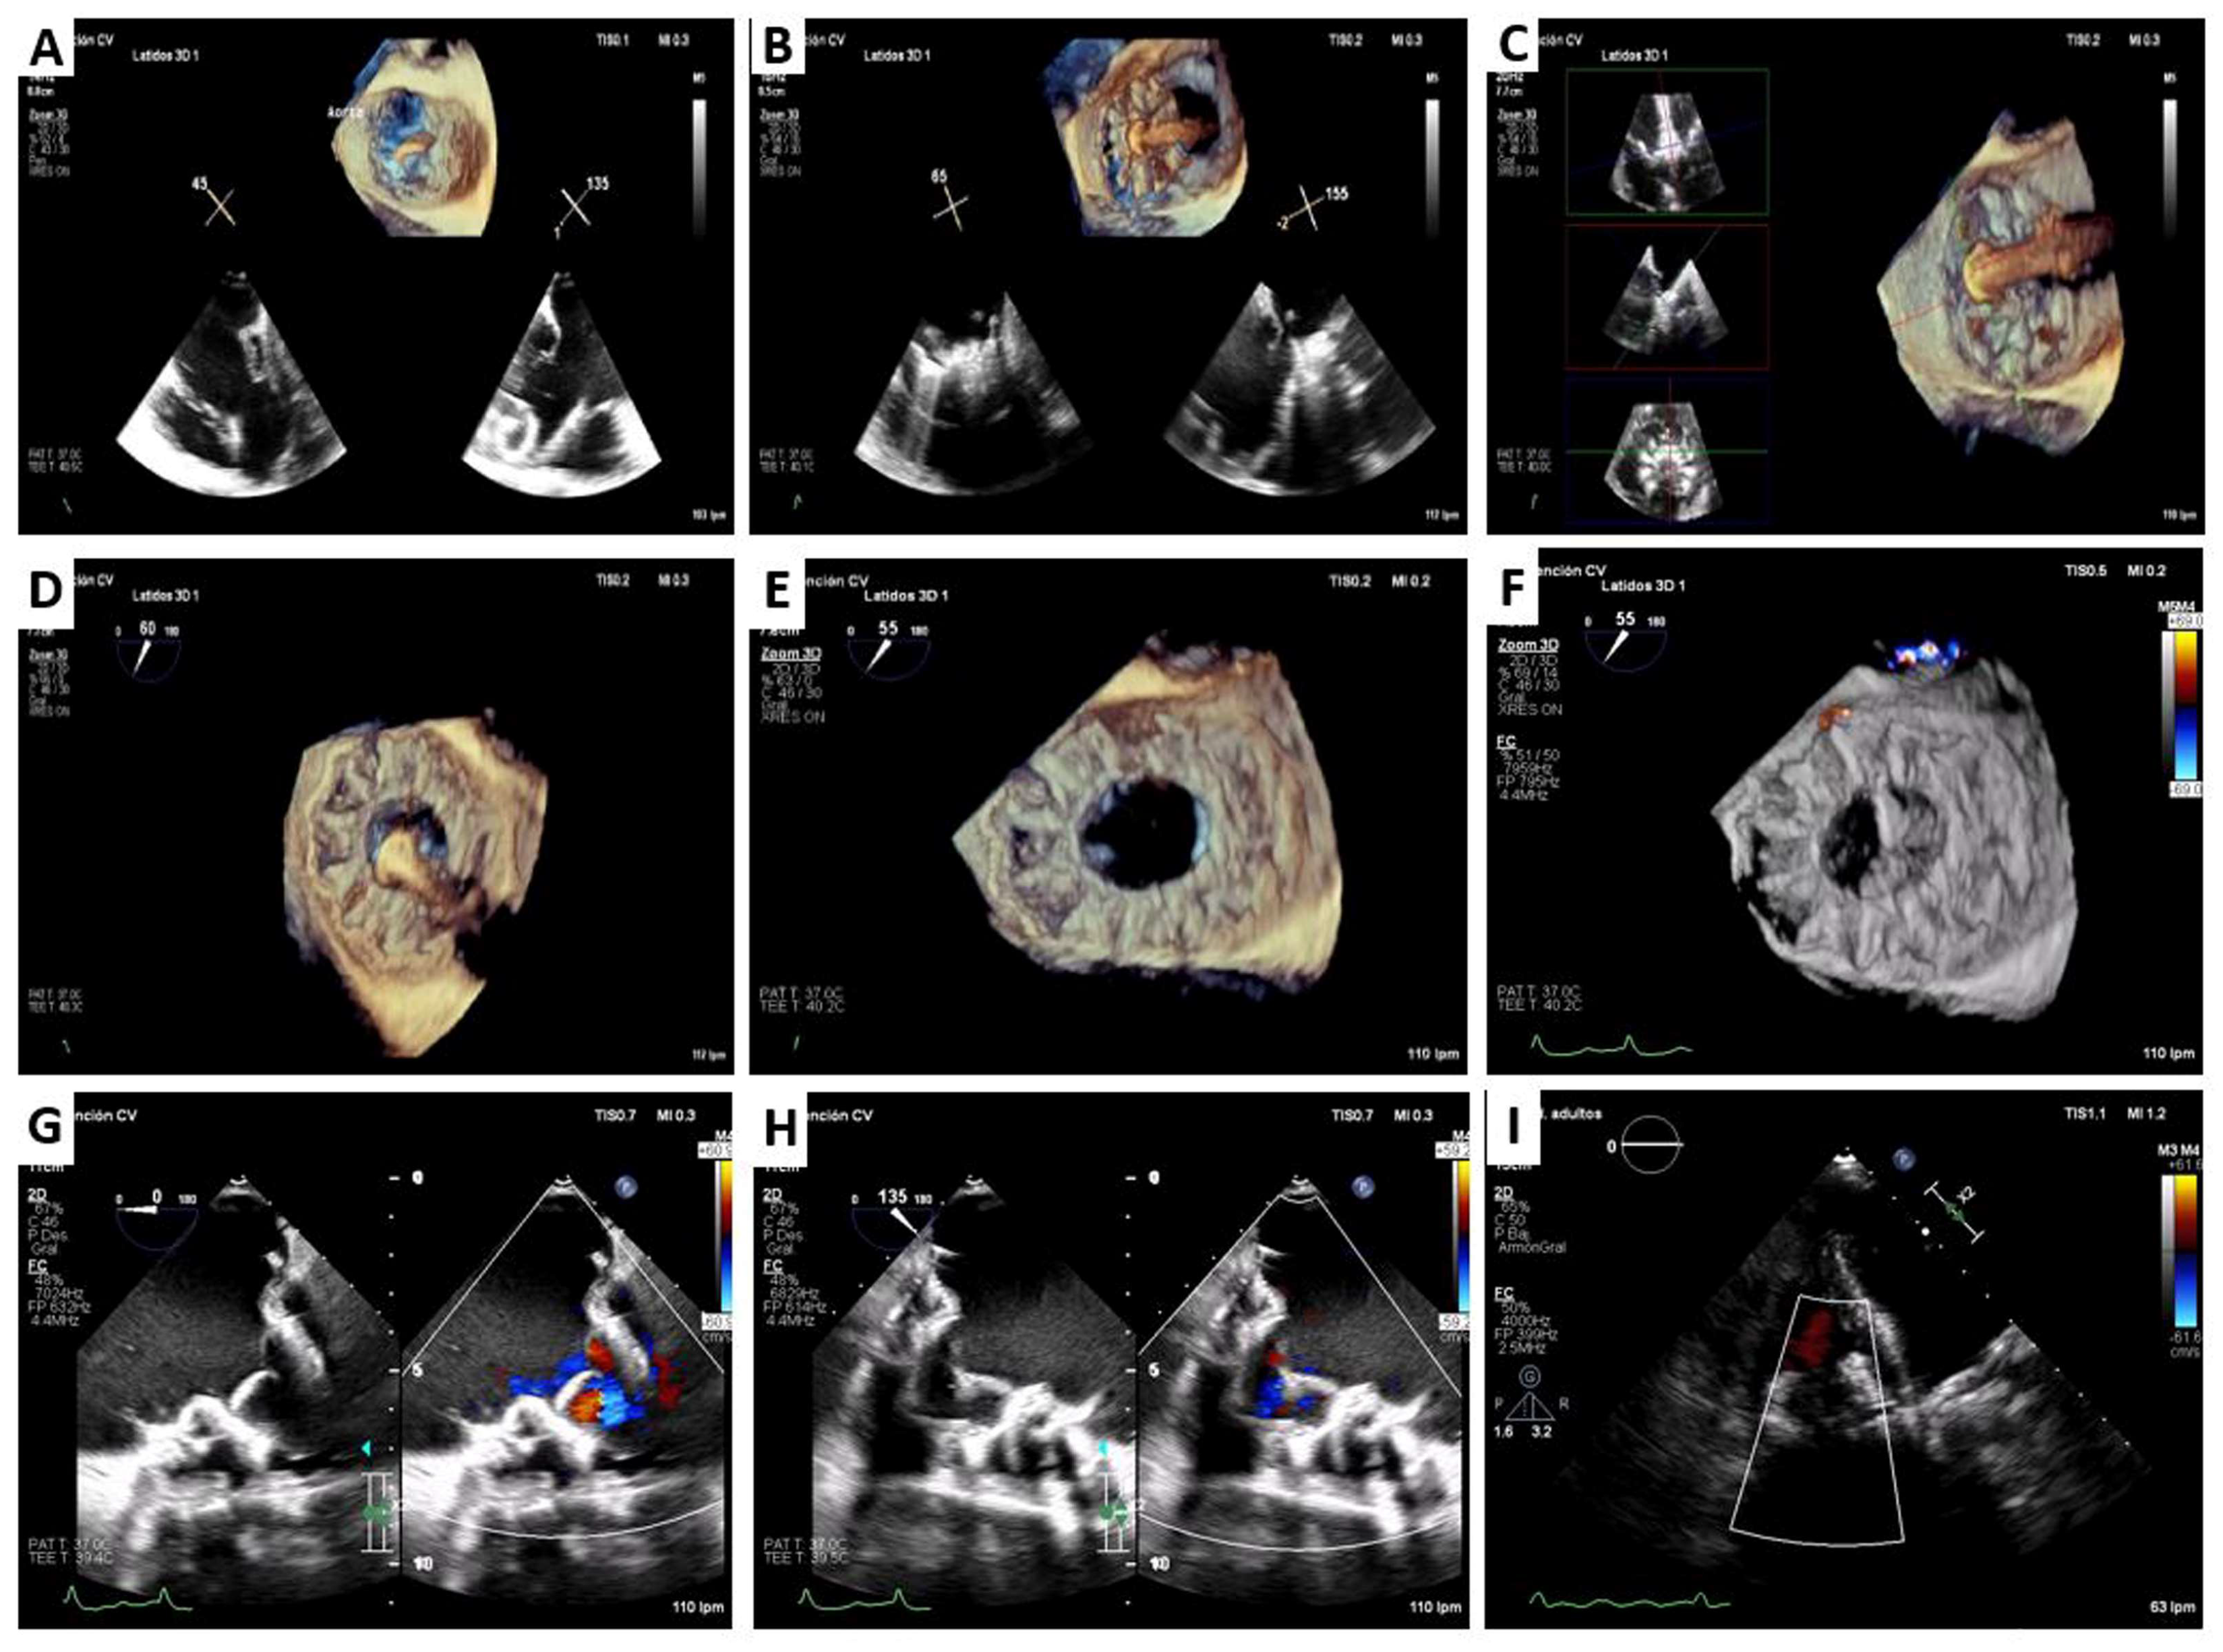

3. Lux-Valve Plus Case

4.4. LuX-Valve

- Zhang, Y.; Lu, F.; Li, W.; Chen, S.; Li, M.; Zhang, X.; Pan, C.; Qiao, F.; Zhou, D.; Pan, W.; et al. A first-in-human study of transjugular transcatheter tricuspid valve replacement with the LuX-Valve Plus system. EuroIntervention 2022, 18, e1088–e1089. [Google Scholar] [CrossRef]